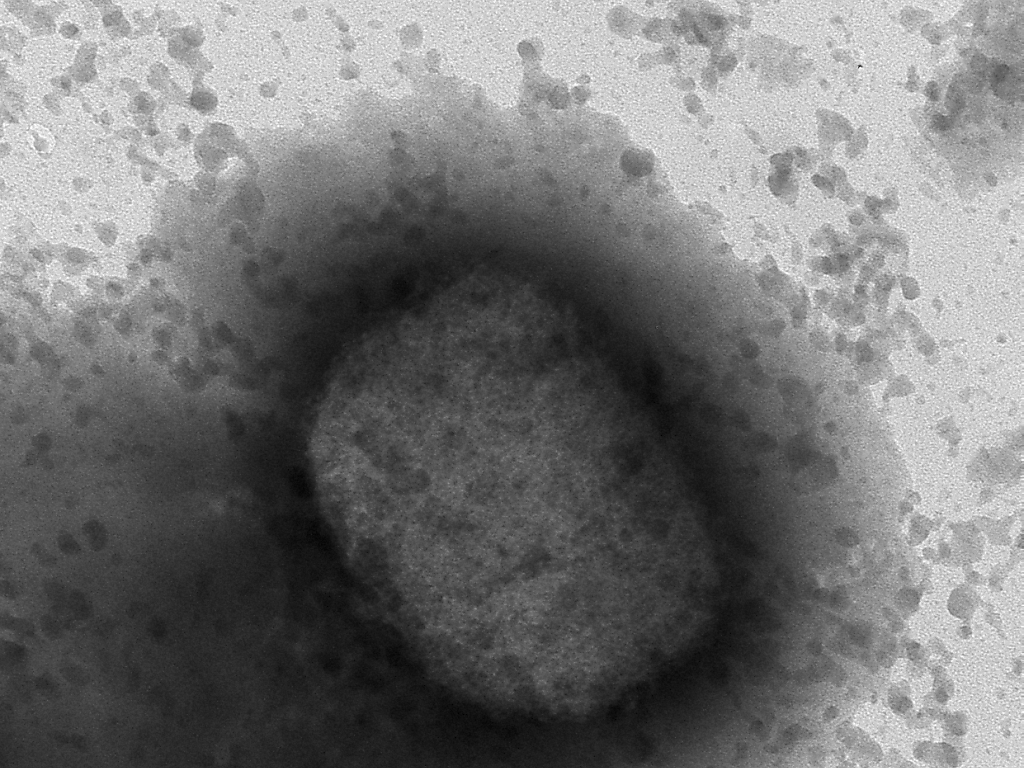

La variole du singe est une maladie infectieuse causée par virus qui se transmet de l'animal à l'humain, mais qui peut aussi se transmettre d'humain à humain. Ces derniers jours, la présence de ce virus rare, endémique dans certaines régions d'Afrique, a été rapportée dans plusieurs pays européens, ainsi qu'aux Etats-Unis.